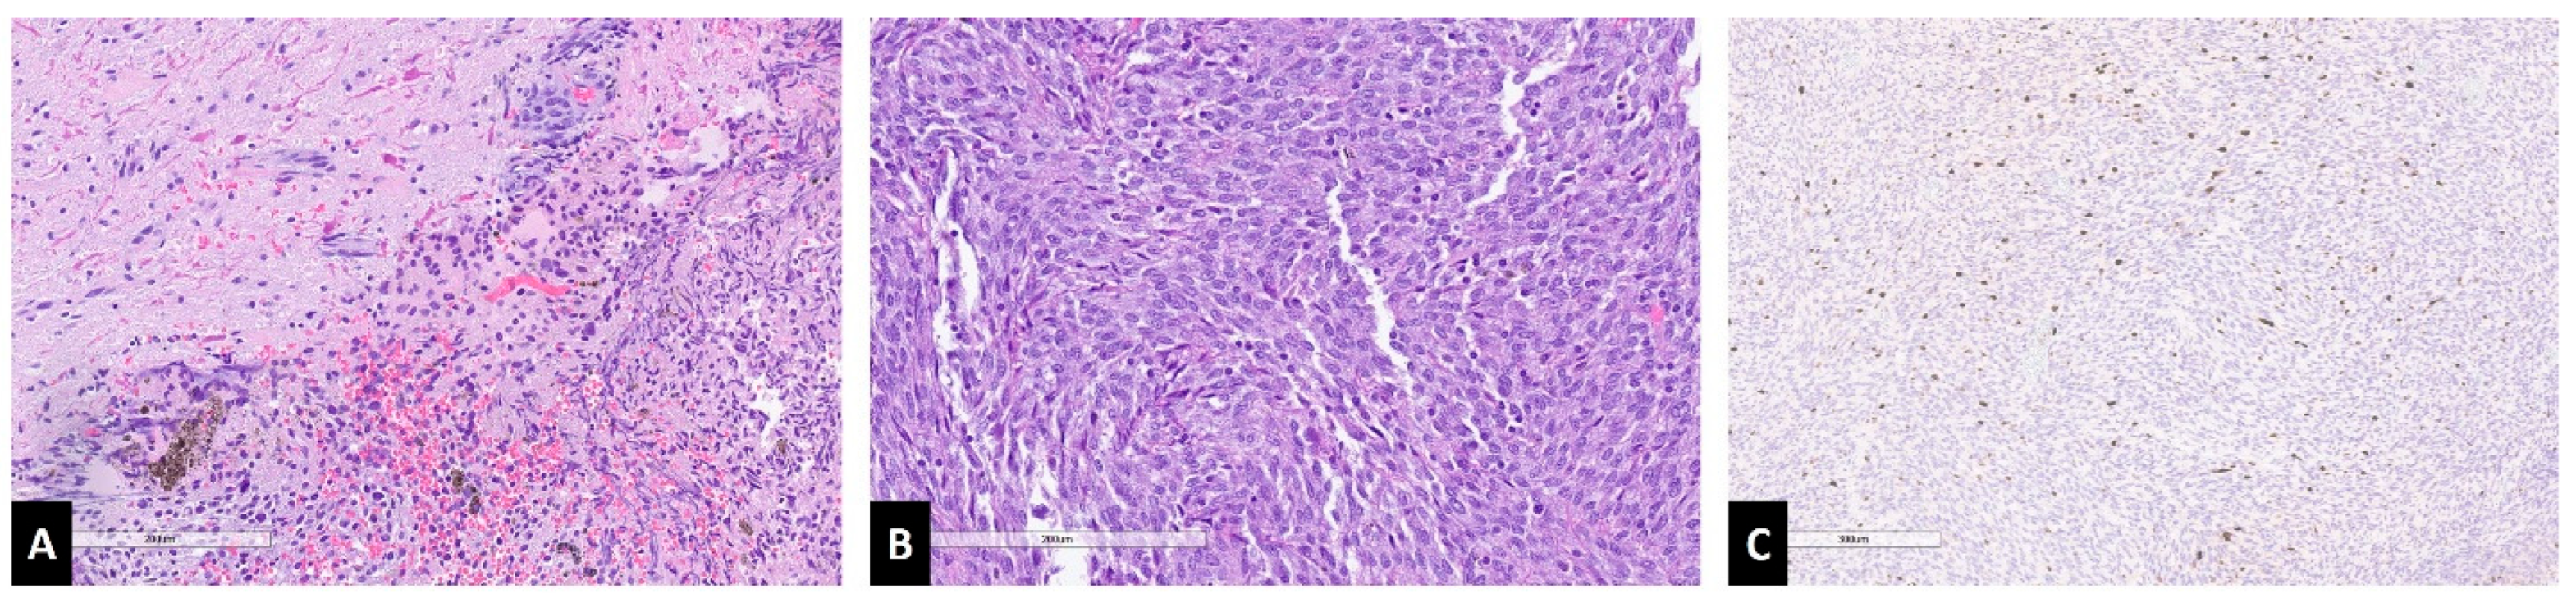

Case Report

4.2. Histopathology and Genetic Markers